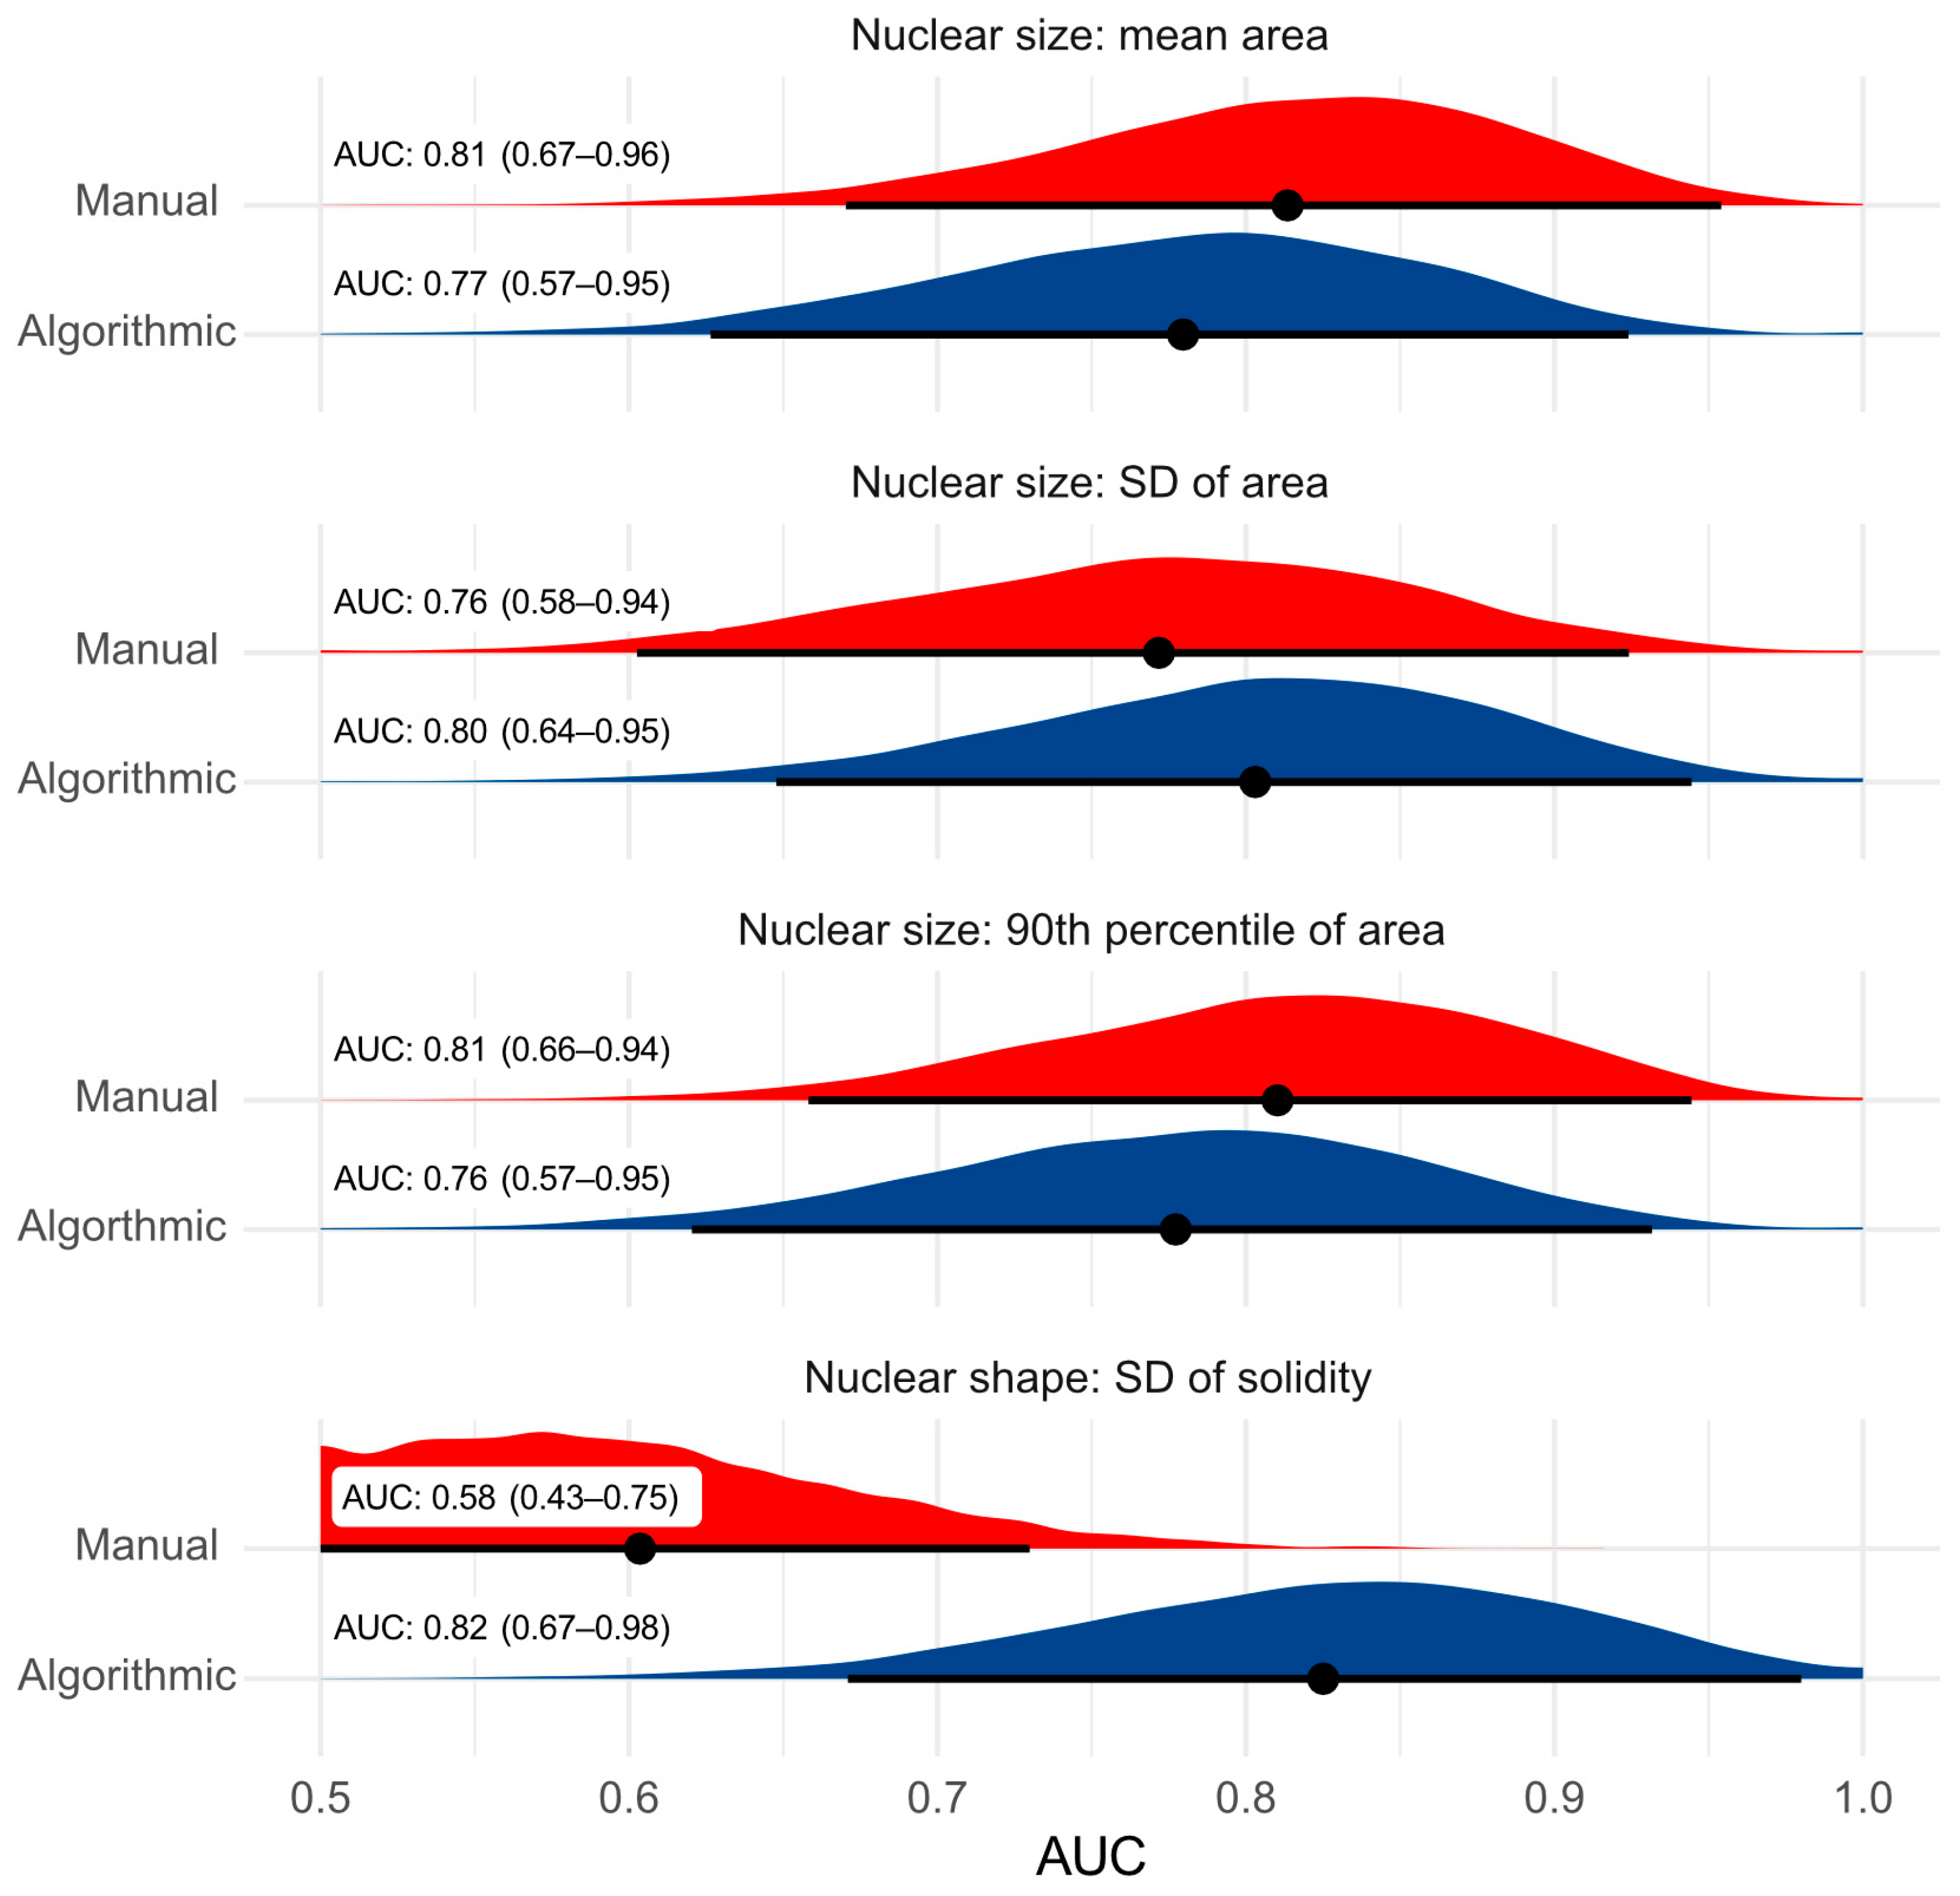

- Algorithmic morphometry is at least equivalent to manual morphometry nuclear pleomorphism estimates (which is impractical for a routine diagnostic test) and other established prognostic tests with regard to prognostic ability.

3.2. Test Accuracy of Algorithmic Morphometry

3.3. Prognostic Value

- Regarding tumor-specific survival, the prognostic ability of the algorithmic morphometry was similar to manual morphometry for most parameters, with the exception of SD of solidity, and other established prognostic tests (histological grade, mitotic count, and clinical staging). The algorithm has the advantage of efficiency as a large number of nuclei can be measured within a few seconds and thus makes morphometry feasible for routine diagnostic service.

4.5. Prognostic Value